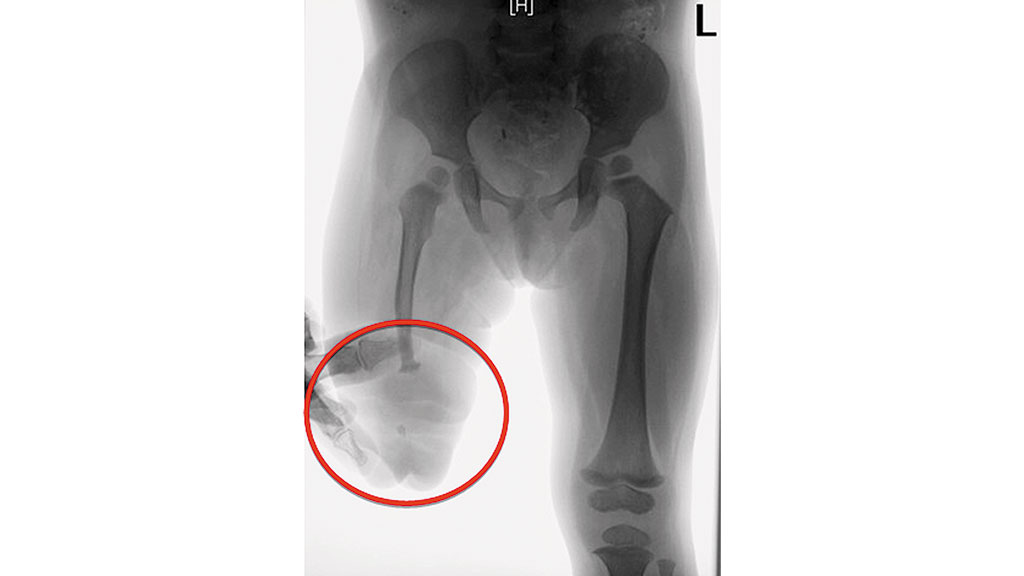

Im zweiten Fall handelt es sich um ein 8‑jähriges Mädchen, das infolge einer intrauterinen Embolie (im 7. Schwangerschaftsmonat) nach der Geburt transfemoral amputiert wurde. Das Erscheinungsbild des Stumpfes wirkt äußerlich wie ein Knie-Exartikulationsstumpf (Abb. 8). Am distalen Femurende waren mehrere Knochensegmente eingelagert, die die Patientin muskulär bewegen konnte (Abb. 9). Das Hüftgelenk wurde zu Beginn der Versorgung mit 10 Monaten als nicht stabil eingestuft.